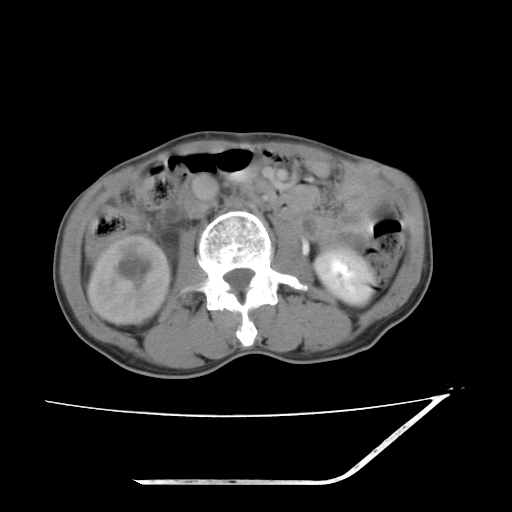

平扫

增强

考虑右肾盂癌,肾动脉受侵,右肾功能减退,右肾盂输尿管积水,管壁增厚,考虑种植转移,应该把下面扫完的

支持右侧肾盂癌伴肾静脉瘤栓形成可能性大,右肾结石.肝右叶后段低密度影,不除外转移.

右肾囊实性占位,支持肾癌,窗宽窗位不是很理想

右肾盂旁ca并肾静脉瘤栓形成/肾功能降低。

右肾结石。

右肾盂癌,肾动脉受侵,右肾盂输尿管积水,管壁增厚,考虑种植转移

1.右侧肾盂癌伴肾盂积水。

2.肾脏功能减退,原因有:(1)肾动脉受侵。(2)肾静脉受侵(3)肾积水,等。本例,肾动脉显影较好,但受压明显;肾静脉无明显显示,受压或静脉癌栓,下腔静脉腔内未见明显充盈缺损。